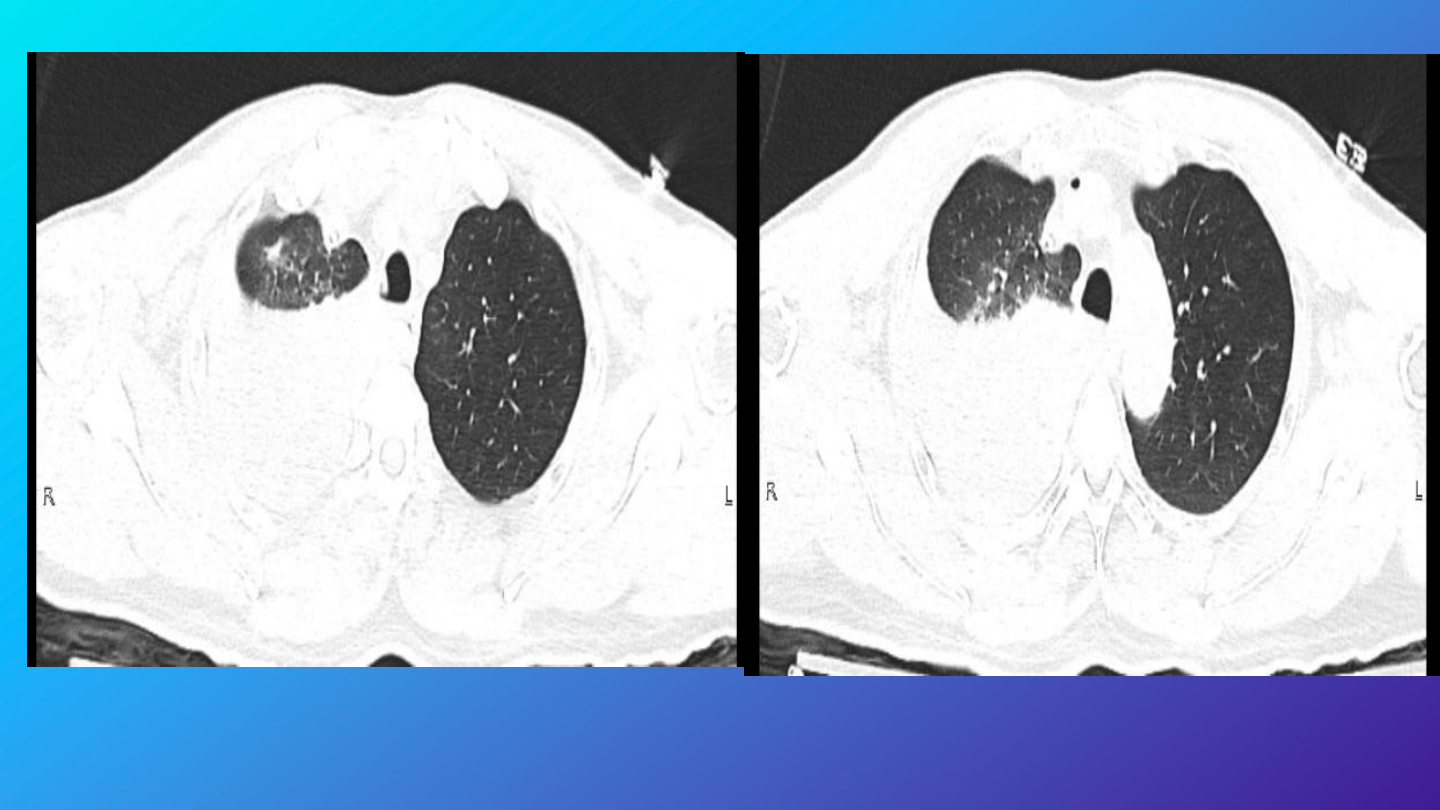

急诊完善胸腹部

CT

检查

结果:

右肺中下叶及左肺下叶炎性渗出,右侧胸腔

积液,建议治疗后复查。

左肺各叶数枚良性小结节及钙化灶。

右侧第

6

肋骨骨皮质褶皱。

肝内数枚囊肿。右侧腹股沟管增宽,部分脂

肪疝出。